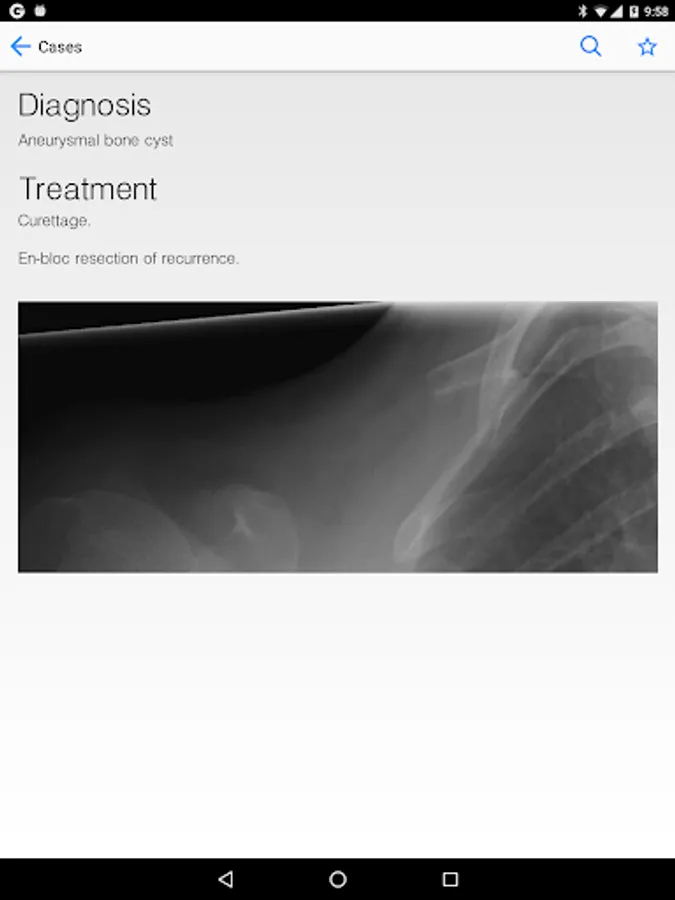

BoSTT brings the user a real experience of frequent and rare, typical and more unusual cases of bone and soft tissue tumours. Each case has a clinical history, high resolution radiology and pathology images, diagnosis, treatment and learning points.